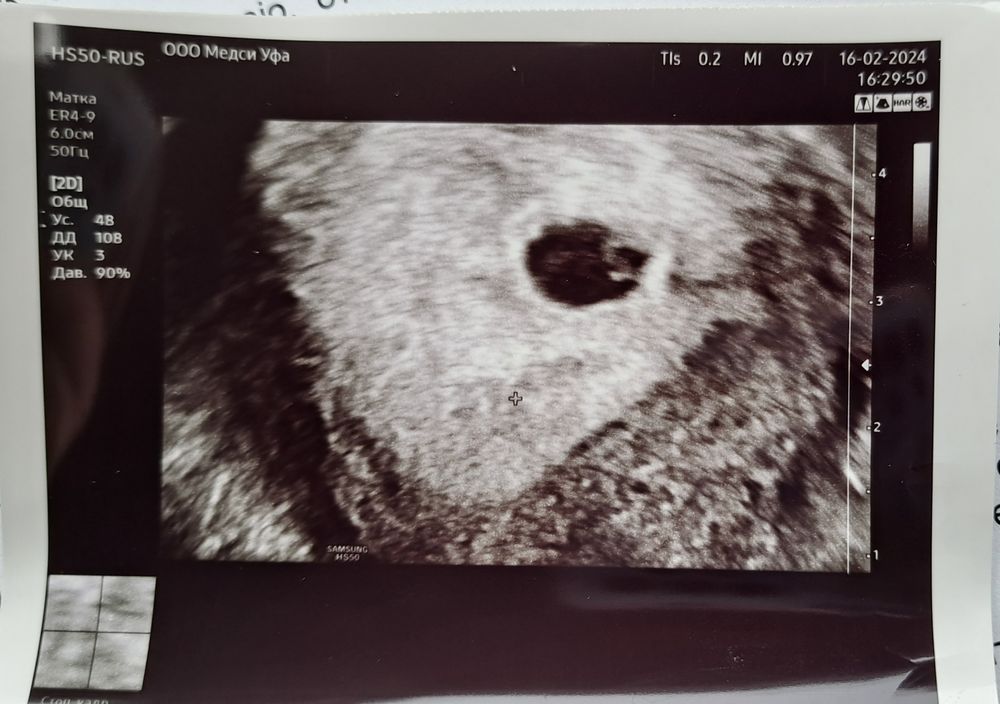

16.02 сделала узи платно для постановки беременности. Плодное яйцо 13.5, желточный мешочек 4 мм, ктр 2 мм. Срок: 4 недели. Обнаружили какое-то жидкостное содержимое в матке, не описали. Гинеколог направила сделать узи 19.02 в жк. Я сходила, но не понятно ничего: плодное яйцо 14.8, срок аш 6.2 недели, не обнаружили желточный мешочек и эмбриона + ретрохориальная гематома.

Добрый день! Делать узи на ранних сроках в разных клиниках-то ещё сомнительное удовольствие: разные аппараты, разные врачи "расшифровщики".На фото от 16.02 вижу желточный мешок. Я бы через неделю повторила УЗИ и желательно там же, посмотрев динамику